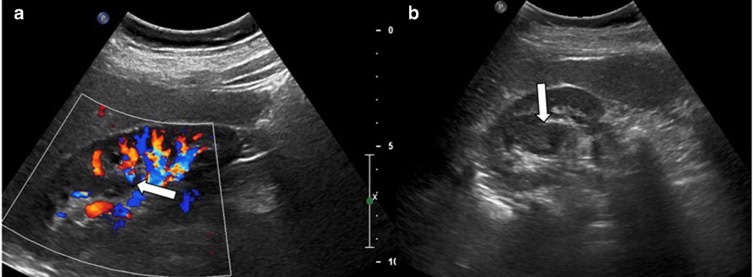

- Malformation artérioveineuse rénale